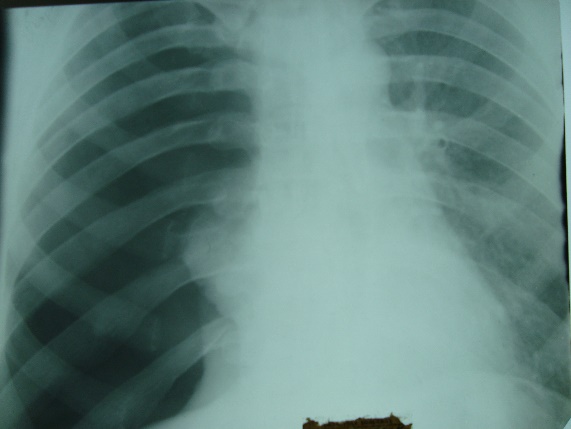

Какой патологический процесс в легких вы видите// Пневмония// Пневмоторакс// +гидропневмоторакс// Плеврит// рак легкого